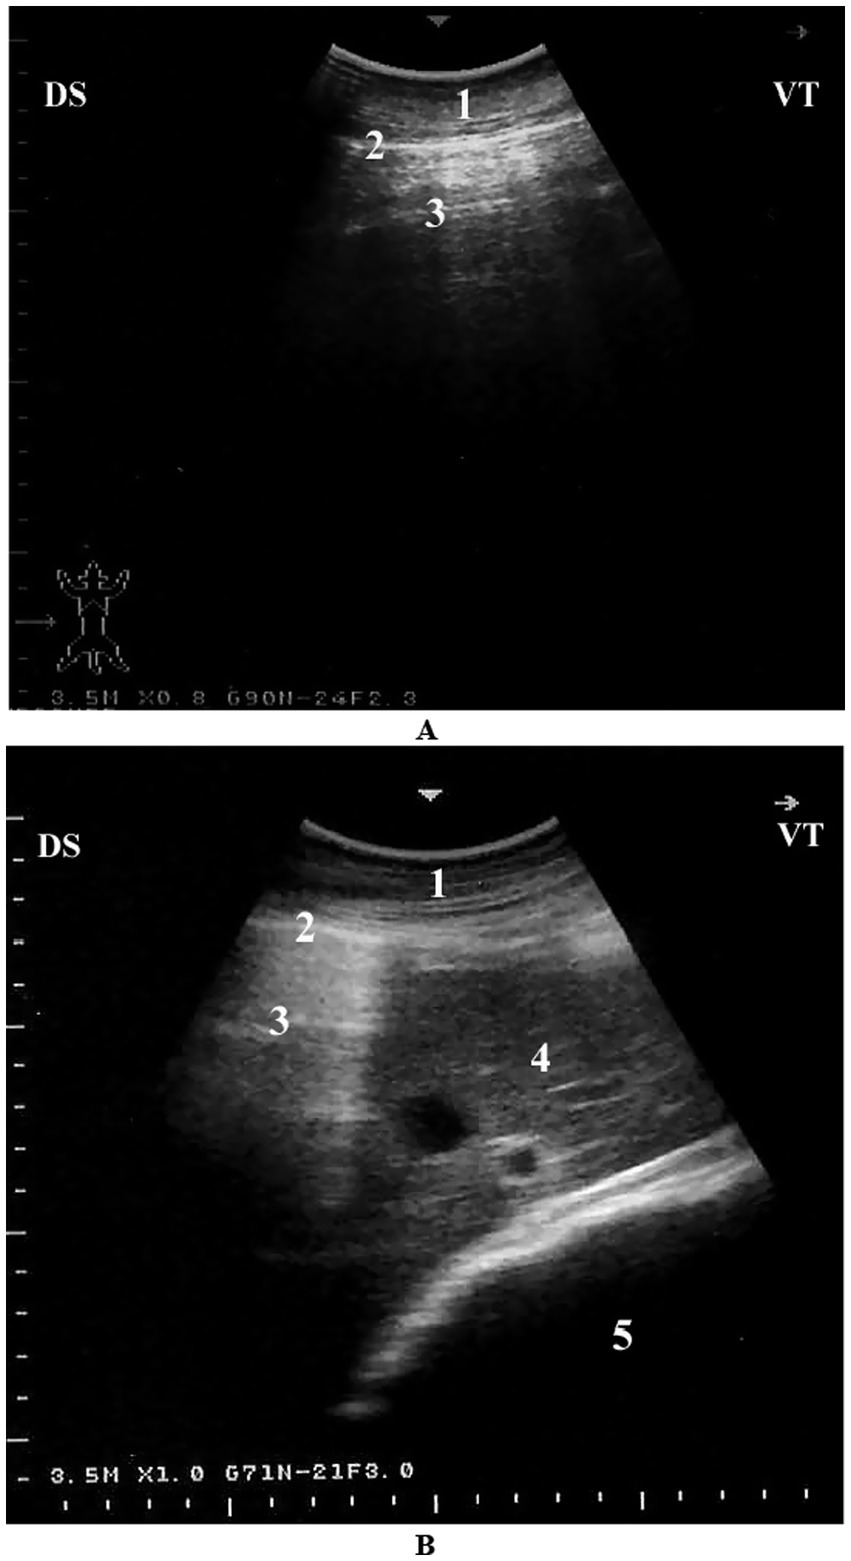

Sonographically, the pulmonary surface is visible from the 4th to the 11th intercostal spaces. The dorsal border of the lung maintains a relatively consistent distance from the dorsal midline. However, between the 4th and 7th intercostal spaces, the dorsal portion of the lung is obscured by the scapula, increasing the distance to the dorsal midline in these regions. The ventral lung border follows a caudodorsal trajectory, resulting in a progressive decrease in the distance between the dorsal midline and the ventral lung border from cranial to caudal. This border is most extensive at the 4th ICS and narrowest at the 11th ICS. The dorsoventral dimension of the lung is greatest at the 8th ICS and gradually diminishes both caudally beyond the 11th ICS and cranially toward the 4th ICS (Table 1). It is important to note that the measured lung size in these intercostal spaces reflects only the portion accessible to ultrasonographic examination and does not represent the actual lung dimensions. The echogenic line visible on the lung surface, formed by the costal and parietal pleurae, measures approximately 1 to 4 mm in thickness (7) (Figure 6). Recognizing these normal ultrasonographic features is essential to avoid false-positive interpretations and to serve as a comparative baseline for detecting pulmonary pathology in clinical and field settings.

Figure 6. Normal lung ultrasonography in a camel. (A) Intercostal view from the right 8th intercostal space showing a typical reverberation pattern beneath the pleural line. (B) Cross-sectional image from the right 6th intercostal space showing normal lung (with reverberation), liver, and omasum. 1 – Thoracic wall; 2 – Pleura; 3 – Reverberation artifacts; 4 – Liver; 5 – Omasum; Ds – Dorsal; Vt – Ventral [modified from Tharwat (7)].